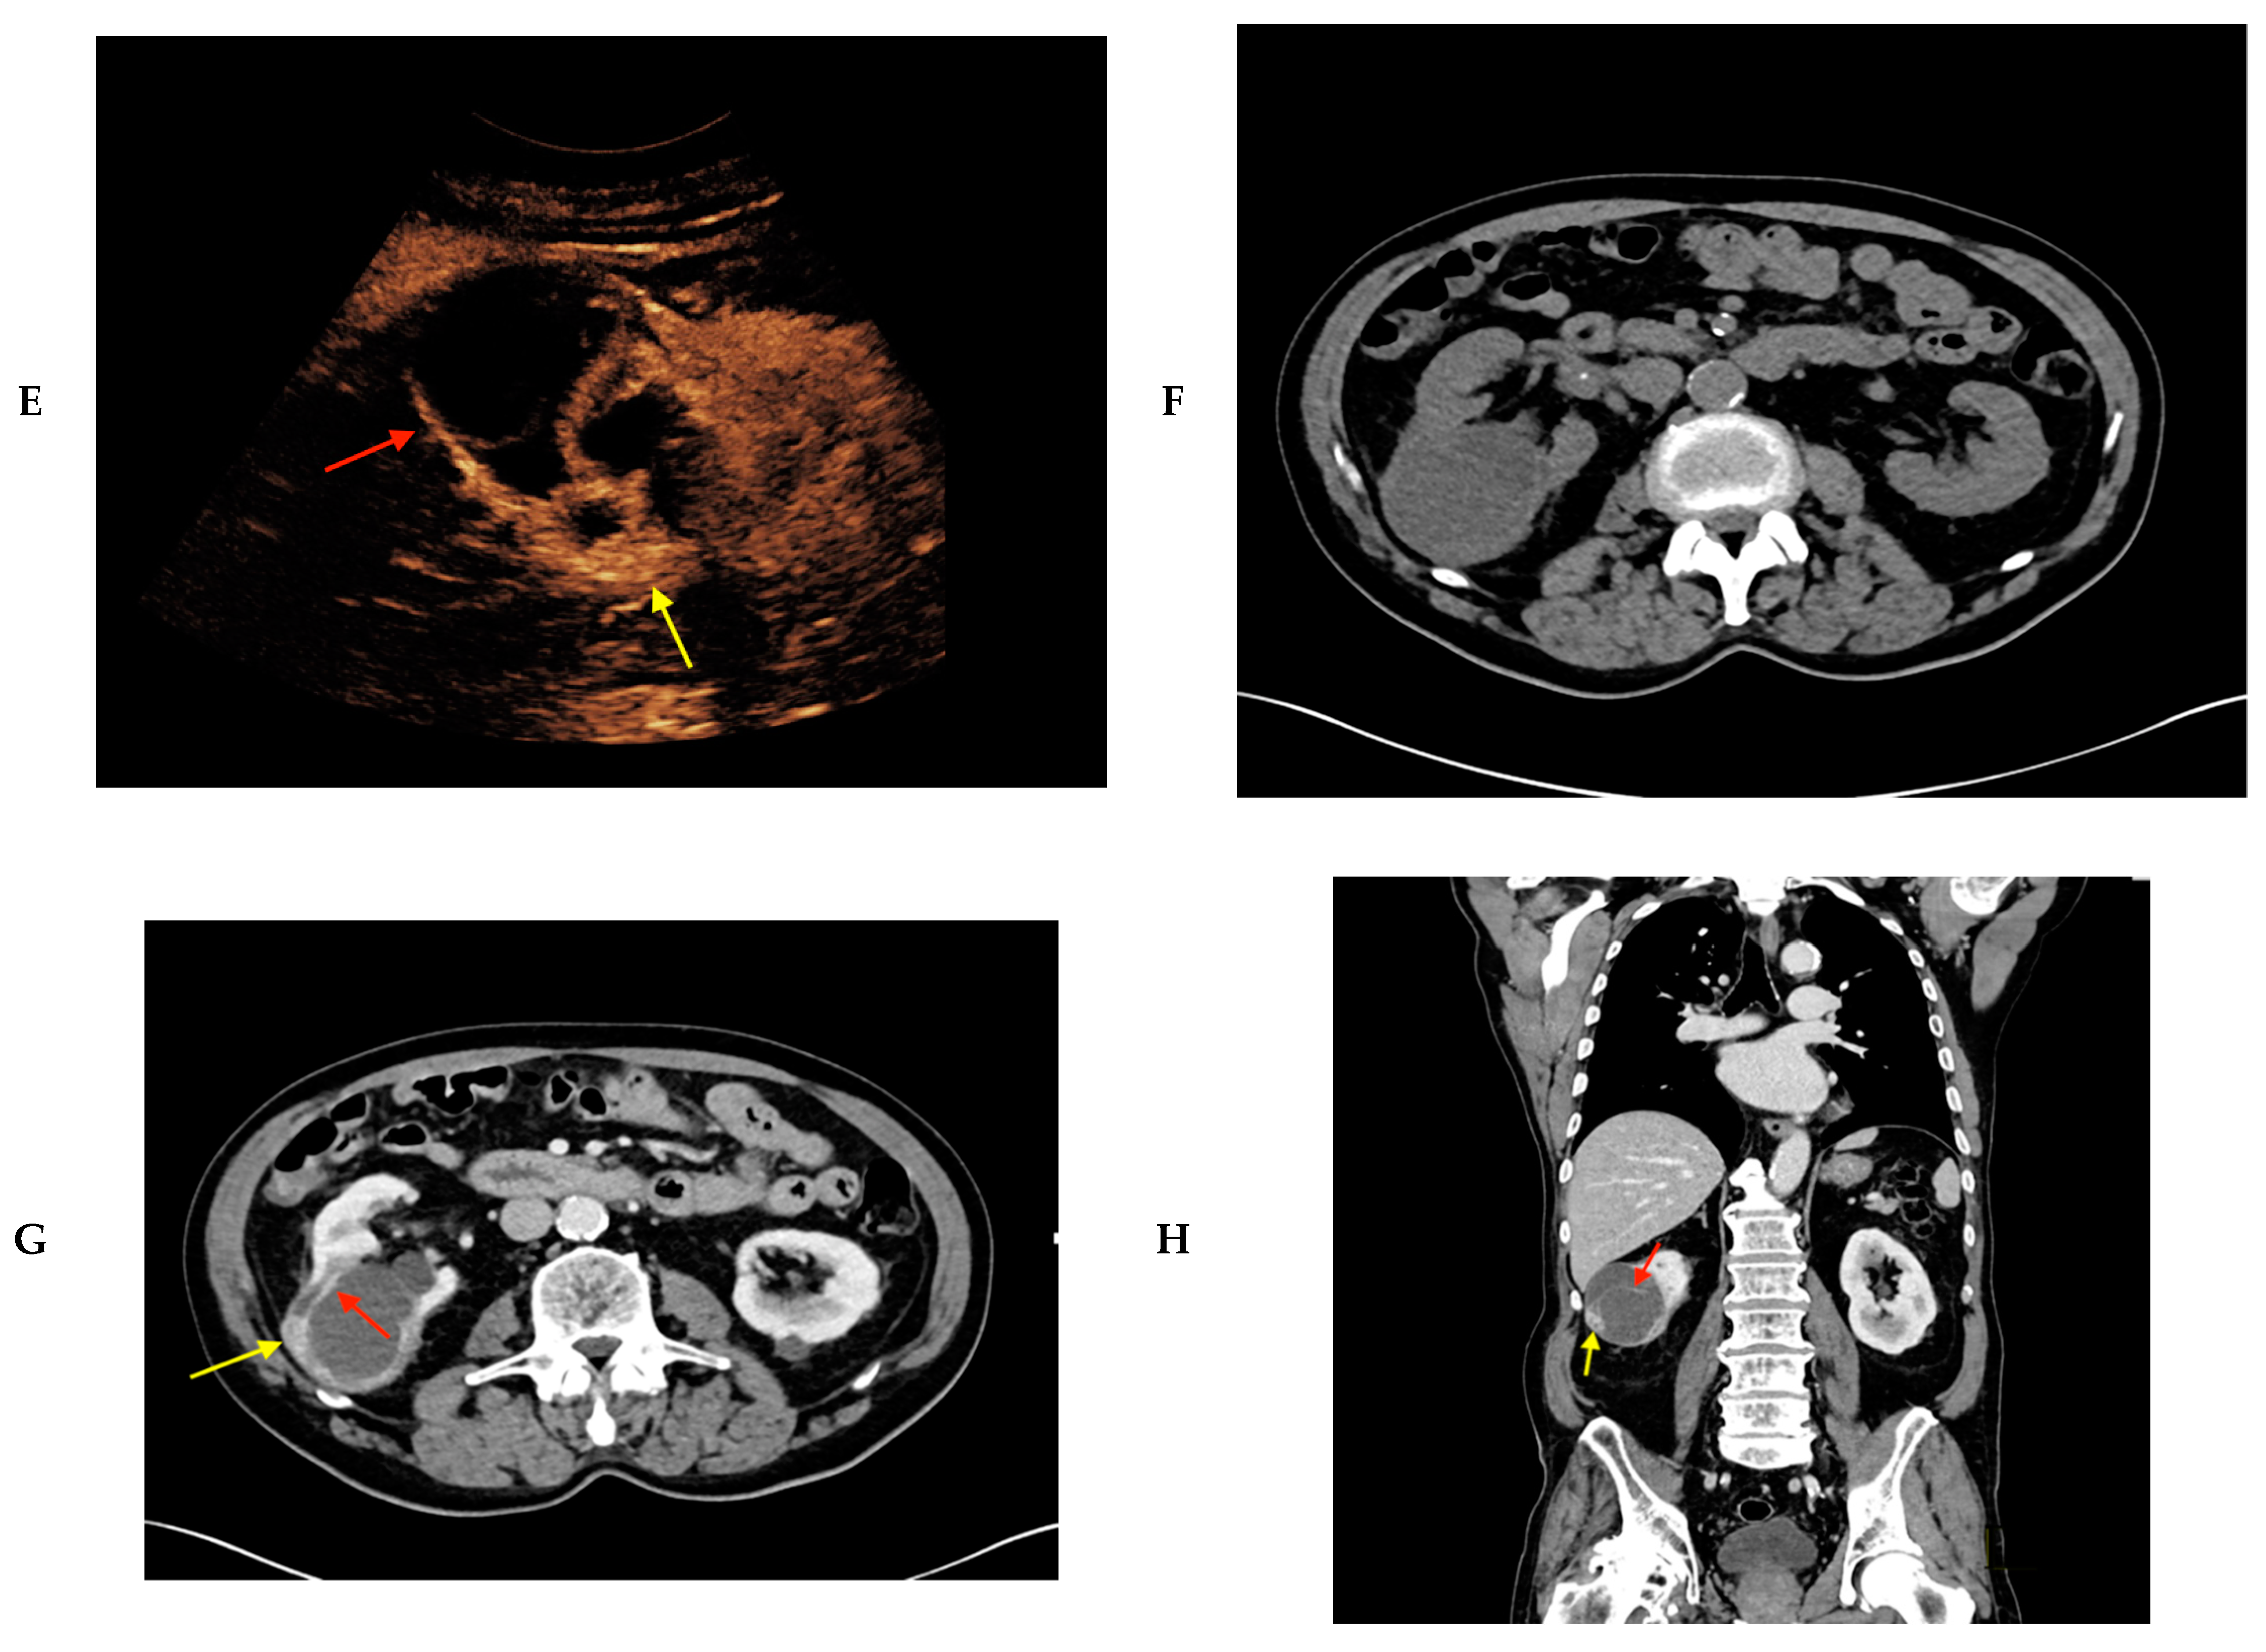

2. Results

4. Materials and Methods

- Rubenthaler, J.; Wilson, S.; Clevert, D.A. Multislice computed tomography/contrast-enhanced ultrasound image fusion as a tool for evaluating unclear renal cysts. Ultrasonography 2019, 38, 181–187. [Google Scholar] [CrossRef] [PubMed]

- Rubenthaler, J.; Paprottka, K.J.; Marcon, J.; Reiser, M.; Clevert, D.A. MRI and contrast enhanced ultrasound (CEUS) image fusion of renal lesions. Clin. Hemorheol. Microcirc. 2016, 64, 457–466. [Google Scholar] [CrossRef] [PubMed]

- European Society of R. Abdominal applications of ultrasound fusion imaging technique: Liver, kidney, and pancreas. Insights Imaging 2019, 10, 6. [Google Scholar] [CrossRef] [PubMed]